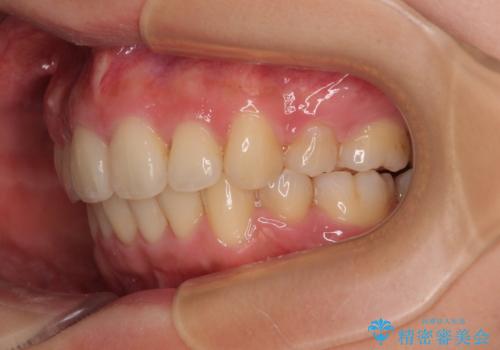

全顎的なデコボコと口元の突出感 ワイヤー装置での抜歯矯正で整った口元に

前歯の突出感がなくなり、仕上がりには大変満足していただけました。

想像以上に咬合力が強く、抜歯したスペースを閉じきるまでに長期間を要することとなりました。